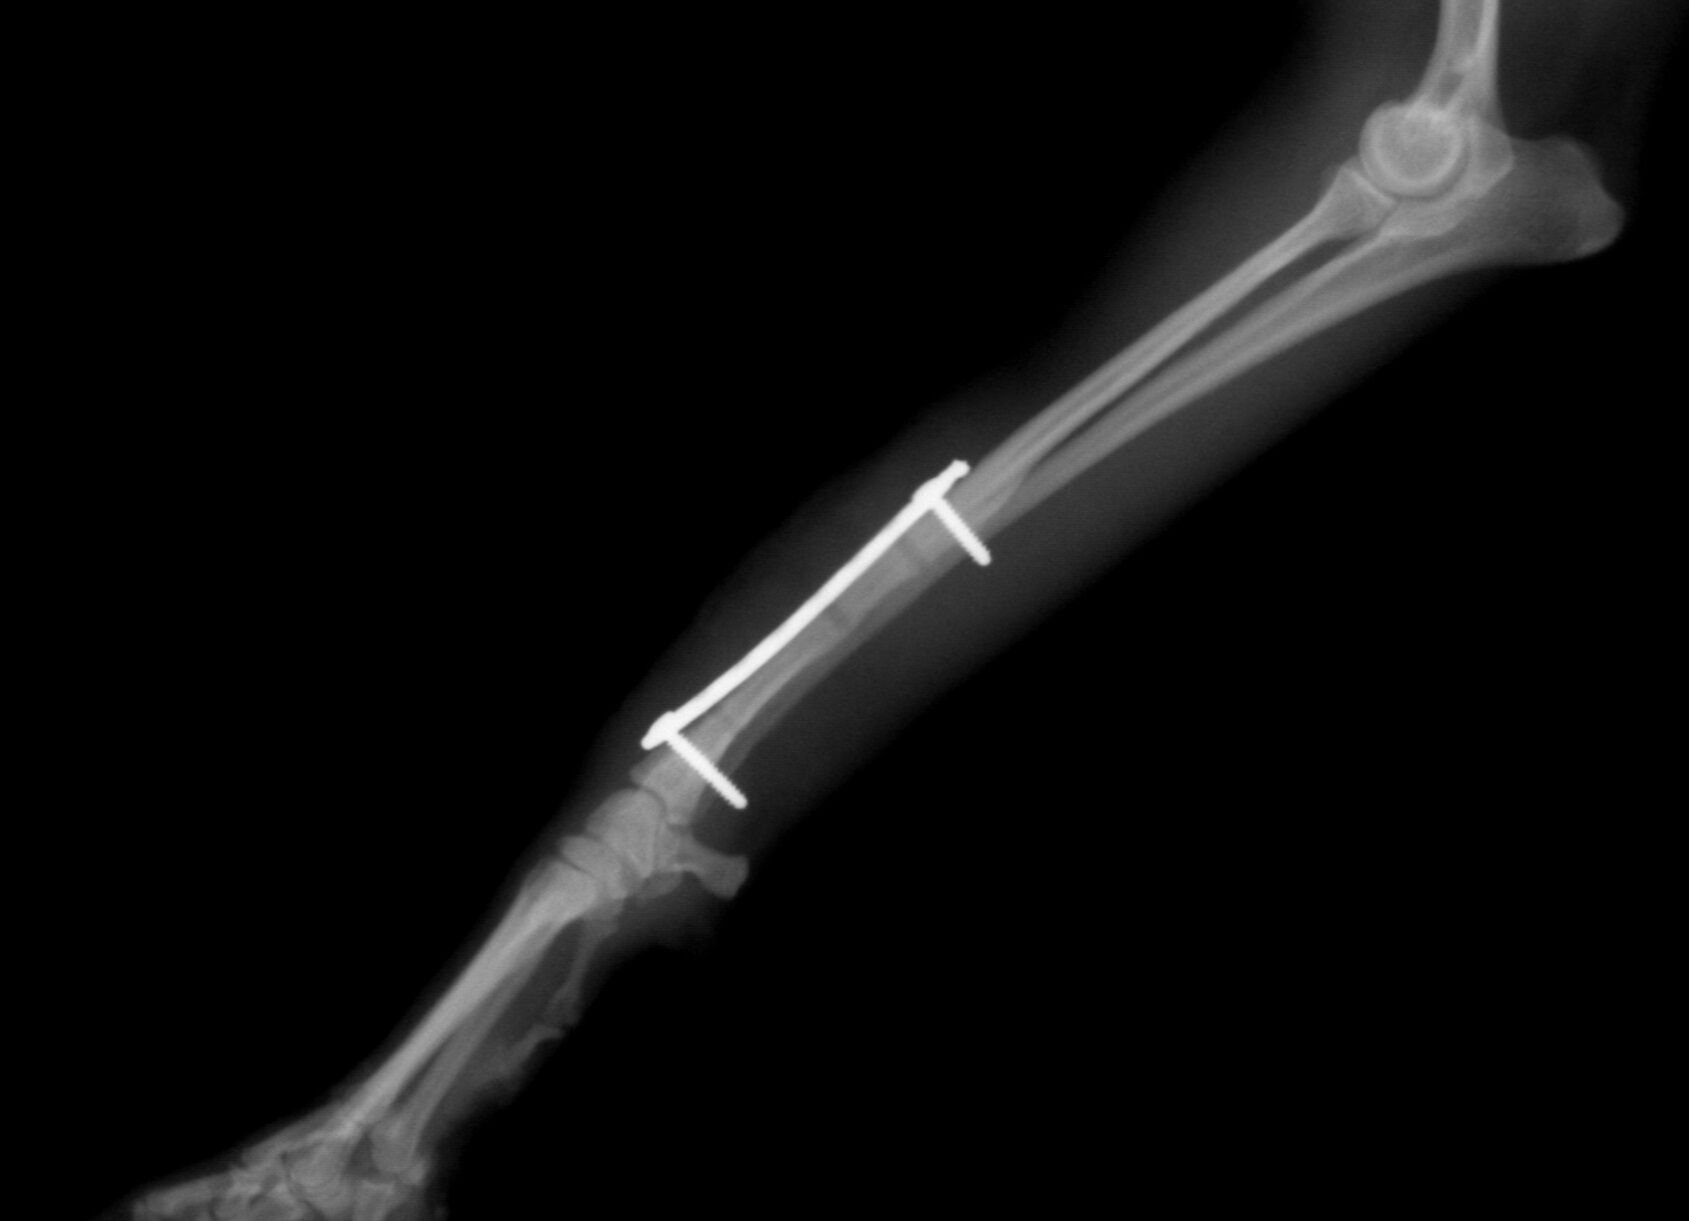

こんばんは、フジタどうぶつ病院です。今日はトイ・プードルの橈尺骨骨折の治療についてご報告させて頂きます。トイ・プードルは脚が長く、骨が細いので非常に骨折が多い犬種です。椅子やソファーから降りた時に折れたり、中には飼い主さんの後ろを歩いていて気づいたら脚を挙げていて病院でレントゲンを撮ったら折れていた、ということもあるようです。今回の症例報告のワンちゃんは椅子から降りた時に折れてしまったようです。下の写真が病院に来院時に撮ったレントゲン写真です。前脚の橈骨と尺骨が折れています。